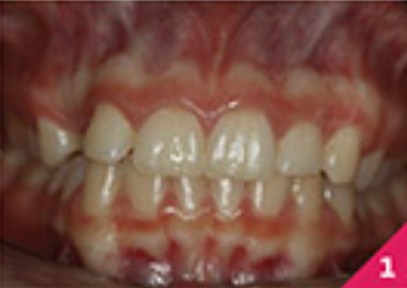

В пацієнтки не було жодних проблем зі здоров'ям та стоматологічних захворювань, крім, мінімальної гіпертрофії ясен на центральних різцях нижньої щелепи. Дотримання гігієни ротової порожнини було відмінним. У пацієнтки був скелетний I клас зі співвідношенням на молярах по I класу.

Праве ікло верхньої щелепи було в перехресному перекритті, а різці верхньої і нижньої щелепи були нахилені. Скупчення зубів було помірним у верхньому зубному ряді та легким у нижньому.

На фото зображено розташування зубів перед початком лікування.